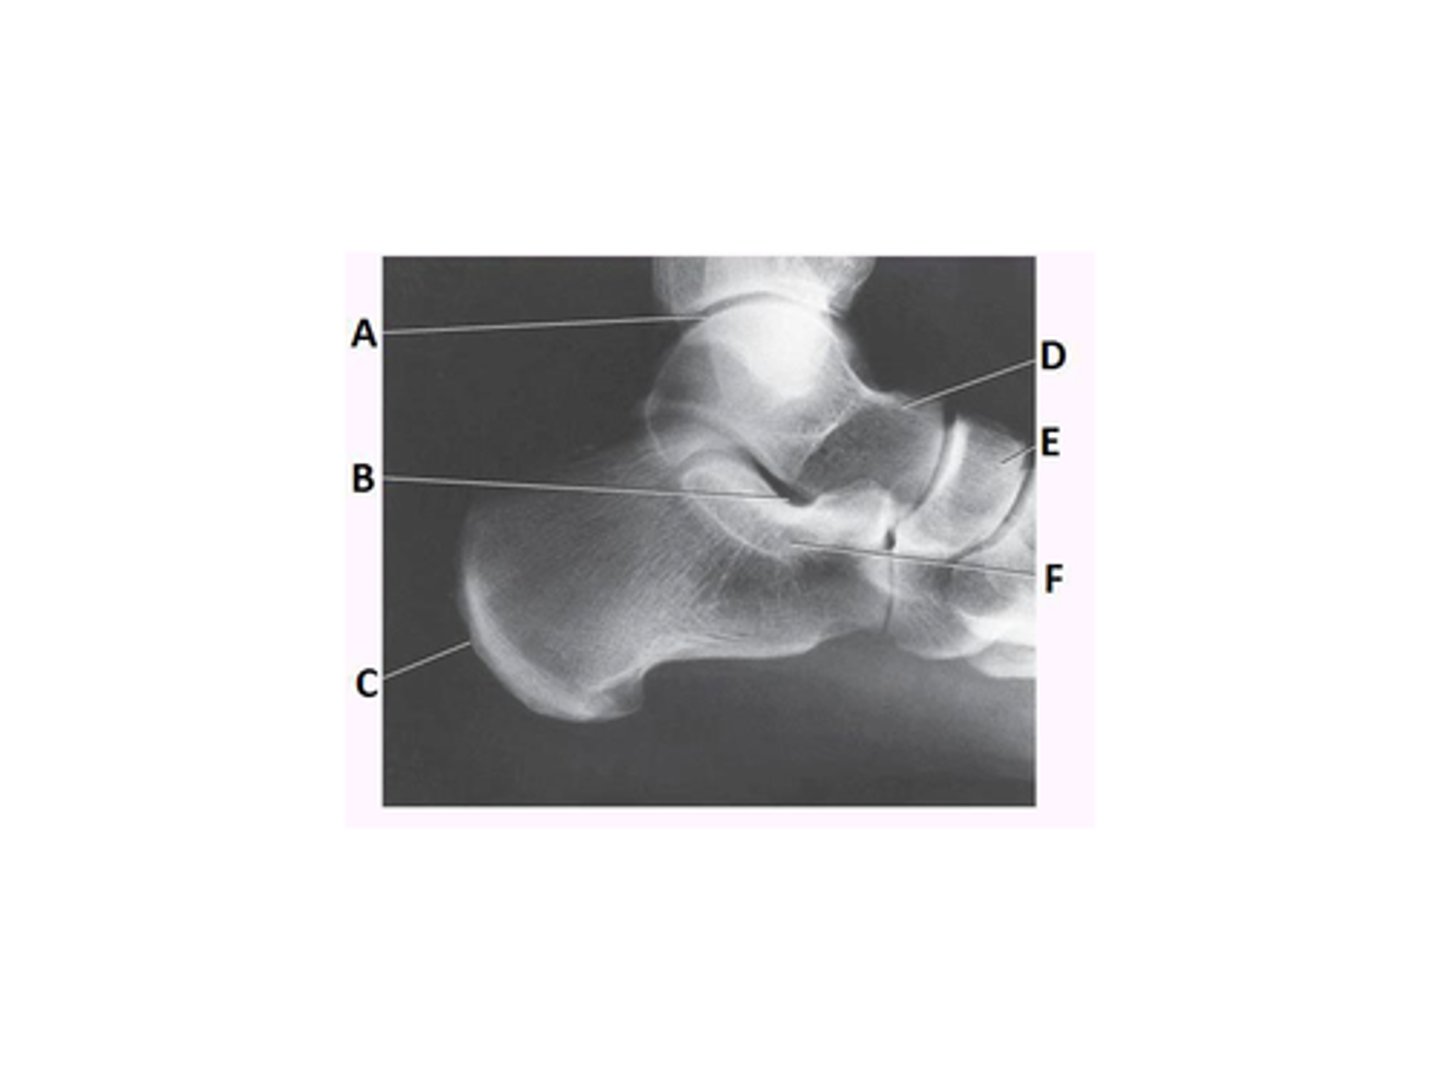

What anatomy is labeled as letter E in the image below?

Mortise joint

Tibiotalar joint

Navicular

Lateral malleolus

What anatomy is labeled as letter D in the image below?

Talus

Sinus tarsi